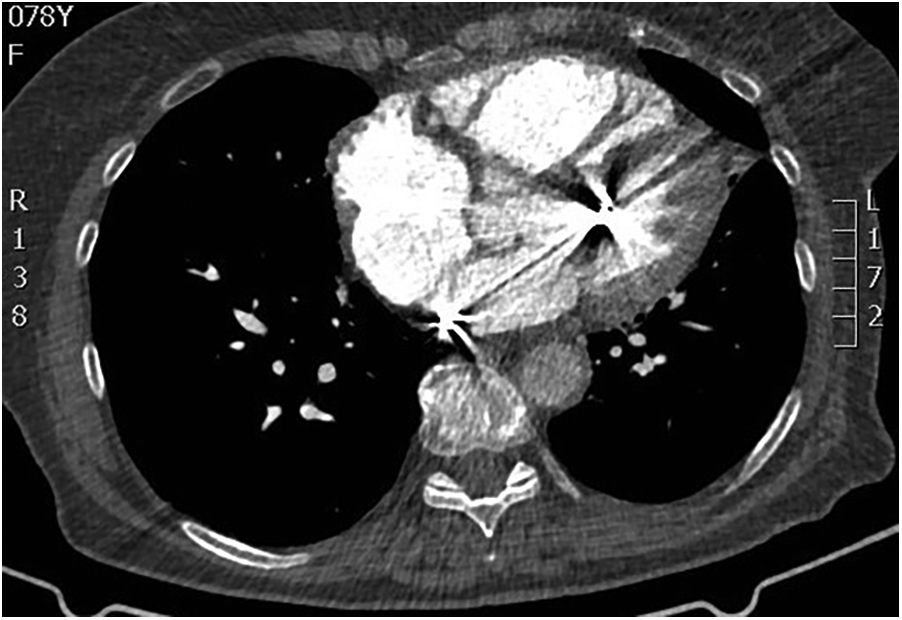

Transesophageal echocardiography (TEE) demonstrated a superior sinus venosus defect near the junction of the superior vena cava (SVC) and right atrium with left-to-right shunting. Two pacing leads pass through the defect from the SVC into the left side of the heart, with one lead affixed to the left atrium roof and the other extending through the mitral valve without any perforations into the left ventricle, where it is fixed to the interventricular septum. No intracardiac thrombi, or “smoke” and thrombi on pacemaker leads were observed during TEE (Figures 2, 3). A contrast-enhanced computer tomography (CT) scan of the chest was performed to further evaluate the suspected congenital defect and confirm the position of malpositioned pacing leads (Figure 4). CT imaging confirmed the presence of a superior sinus venosus defect located near the junction of the SVC and the right atrium. Moreover, CT revealed partial anomalous pulmonary venous return, with the right superior and middle pulmonary veins draining into the SVC. Given the patient's age, moderate frailty, and absence of significant clinical symptoms, a conservative approach was adopted. Lead extraction was not pursued due to high procedural risk. The patient was managed with lifelong oral anticoagulation with warfarin to mitigate the risk of systemic thromboembolism. Surgical correction of the anomalous pulmonary venous return was not indicated, as the patient remained hemodynamically stable without signs of volume overload. Ongoing follow-up includes regular assessment of anticoagulation status, pacemaker function, and clinical condition. The patient remained clinically stable during follow-up. No thromboembolic or bleeding complications were observed. TTE and x-ray demonstrated stable lead positioning within the left heart chambers, without evidence of thrombus formation or endocardial damage. Pacemaker function remained intact with appropriate sensing and pacing parameters.

Figure 3

Short-axis left ventricular transesophageal 3D echocardiographic view showing the transit of the two pacing leads across the atrial septal defect. 3D, three-dimensional.